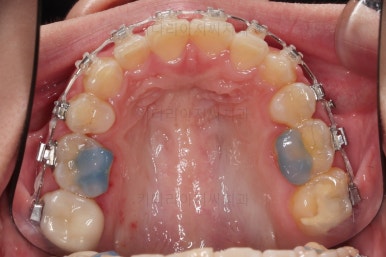

동래교정치과 마무리 사진입니다.

종료 이후에는 어금니의 기존 크라운 보철이 오래되고 탈이나서 재보철을 해주었습니다.

앞니는 비뚠채로 장기간 마모가 되어온 터라 형태가 부적절하긴 한데요.

보철로 마무리하기 보다는 최대한 자연스럽게 시리지 않는 선에서 다듬어 드리고 마무리를 했습니다.